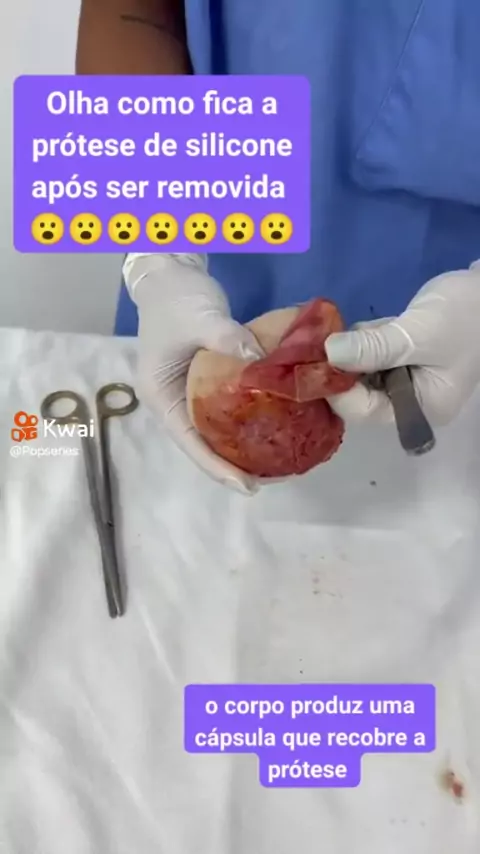

Fique por dentro... #necropsiaeeu #biomedicina #unicesumar #estudante #medicina

Fique por dentro... #necropsiaeeu #biomedicina #unicesumar #estudante #medicina

vc acredita nisso.